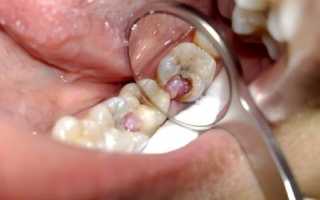

В ней отмечаются жалобы больного, указывается анамнез, то есть история зуба. Врач обязательно отметит: подвергался ли он раньше лечению, есть ли на нем пломба. Также в историю болезни записываются результаты осмотра. Обычно обнаруживается кариозная полость. Зуб имеет белесоватый налет. Пальпация не вызывает болезненных ощущений.